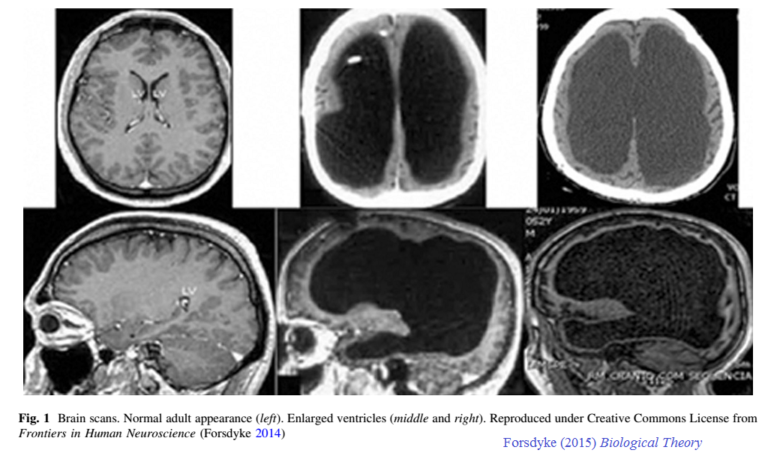

Here, we first dive into well-documented examples of patients with microcephalus, hydrocephalus, hemihydranencephaly, and hemispherectomy, or absence of cortical material, who are missing a large amount of brain matter but tend to lead ordinary lives with average, or above average, intelligence. Such cases demonstrate that brain size, amount of cortical tissue and neuron quantity, even within a single species, do not directly predict intelligence.

Page 10: The neurologist John Lorber identified numerous patients in his medical practice who had severe hydrocephalus as evidenced by their brain imaging results (around 1980). The ventriculomegaly went practically unnoticed and the patients led otherwise normal lives with very little brain tissue. For example, Lorber described a university honors mathematics student who had so much CSF that there was almost no white matter; the ventricular enlargement took up so much space and the actual brain was a thin mantle lining the inner skull. In contrast to the normal thickness of brain tissue between ventricles and outer cortex as being 4.5 cm, this student’s brain mantle measured a mere millimeter or so. Yet, this patient was socially normal, with an IQ of 126 and great academic achievement in math. Lorber’s patients had an utter lack of brain tissue which went totally unnoticed until imaging was taken.

Above, the scans on the left is of a normal brain and the four scans on the right shows the cerebral cavities where cerebral spinal fluid, water mostly, is in place of where brain tissue ordinarily is.